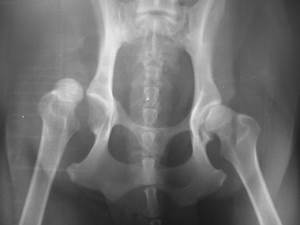

Вывих тазобедренного сустава происходит при смещении головки бедренной кости из вертлужной впадины. Одновременно выявляется разрыв суставной капсулы, связок, часто деструкция кости. Чаще всего вывих происходит при травме, особенно предрасположены собаки с дегенеративными изменениями суставов (дисплазия ТБС).

Для установления степени и характера повреждений проводится рентгенографическое исследование суставов. Чаще всего требуется седация пациента.